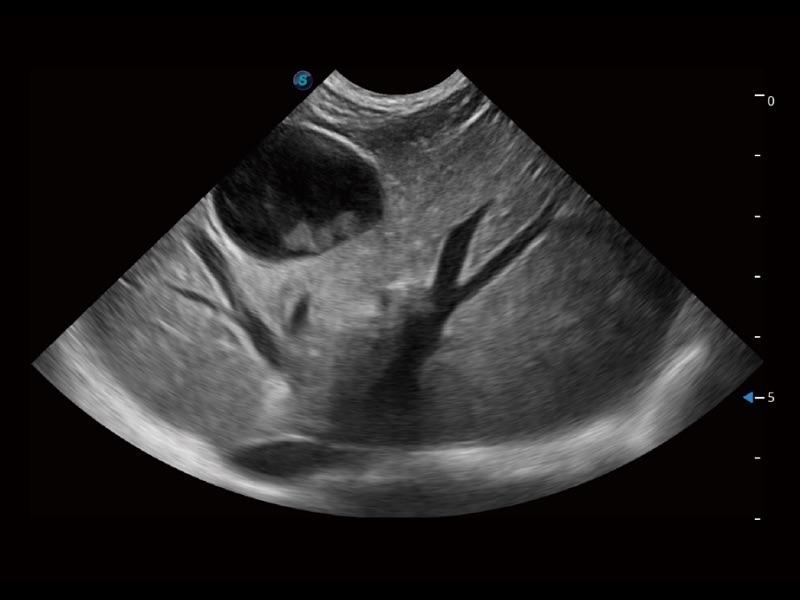

动物是人类最亲密的朋友和最值得信赖的伙伴。milan米兰也一直致力于探索动物专用的超声影像解决方案。全新推出的ProPet系列,是milan米兰在动物超声影像智能化、专业化、精准化的一次跨越式革新。动物不能用言语来表述自己的不适,通过超声影像,ProPet系列搭建了动物医生与不同物种沟通的“桥梁”,为动物医生注入了“治愈之力”。 ProPet 70将是您值得信赖的超声伙伴。它配备了复合材料线阵探头,帮助动物医生获得卓越精准的临床图像。同时ProPet 70直观便捷的操作体验以及专业的测量工具,可为不同体型和生理结构的动物带来全面临床评估,切实为动物医生提供智能、专业、精准的超声影像解决方案。

ProPet 70 进一步提升了微米成像算法,更加注重对基础原始图像的还原和保留,在有效减少斑点噪声、增强组织边界显示的同时,避免过度优化丟失真实的解剖信息。

ProPet 70专为动物医生设计,对不同的动物体型和生理结构作出了针对性的优化。通过动物影像专用软件,可满足个性化的应用需求,帮助动物医生获得更精确的诊断数据。

ProPet 70 全新的动物超声智能软件和丰富的探头群,为动物医生提供了高清晰度和精细分辨率的图像,无论在宠物、马科、畜牧还是实验室动物等应用中都可以轻松应对,为您的日常工作带来满意的体验。